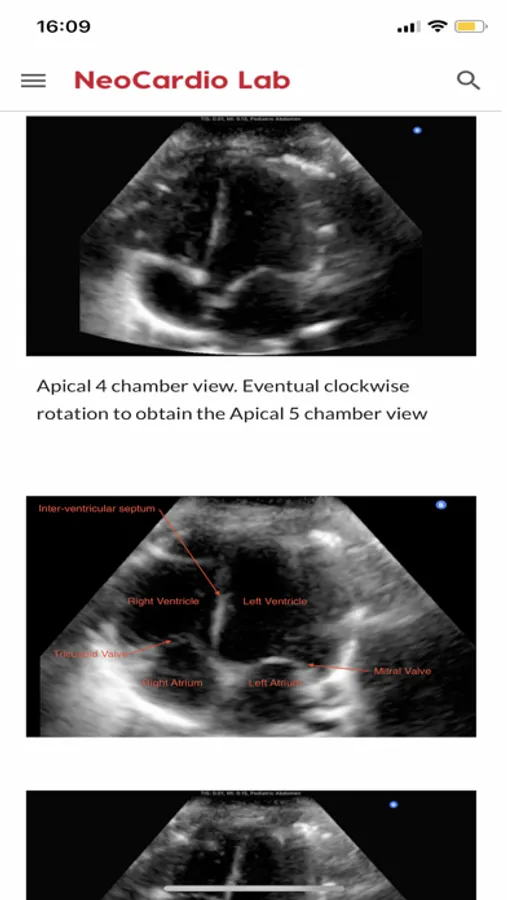

The NeoCardioLab is a research laboratory interested in clinical and epidemiological neonatal cardiovascular research, as well as education in neonatal hemodynamics. The principal investigator of the NeoCardioLab is Dr. Gabriel Altit from the Montreal Children’s Hospital (at McGill University). On the NeoCardioLab website, we have made available for the learners a whole array of content (clips, videos, presentations, reading material, articles, etc.) as a learning opportunity on echocardiography (2D and 3D), TnECHO (targeted neonatal echocardiography), point of care ultrasound (POCUS) and near infrared spectroscopy (NIRS). You will find on the website, our comprehensive “Atlas” for the expected normal complete neonatal echocardiography (with clips of various views and explanations), as well as clips for selected congenital heart defects. Our training modules are: on NIRS in the neonatal intensive care unit, as well as on POCUS/TnECHO. We offer modules on TnECHO (Targeted Neonatal Echocardiography; with clips outlining all the views and measurements, pulmonary hypertension, PDA, normative values, etc.), POCUS (as well as the example of the use of a hand-held device and how to obtain views) and Congenital Heart defects, as well as modules on Strain/Speckle Tracking and Near Infrared Spectroscopy. We also now host the Neonatal NIRS consortium page and all the recordings of their webinars.

NeoCardioLab Screenshots